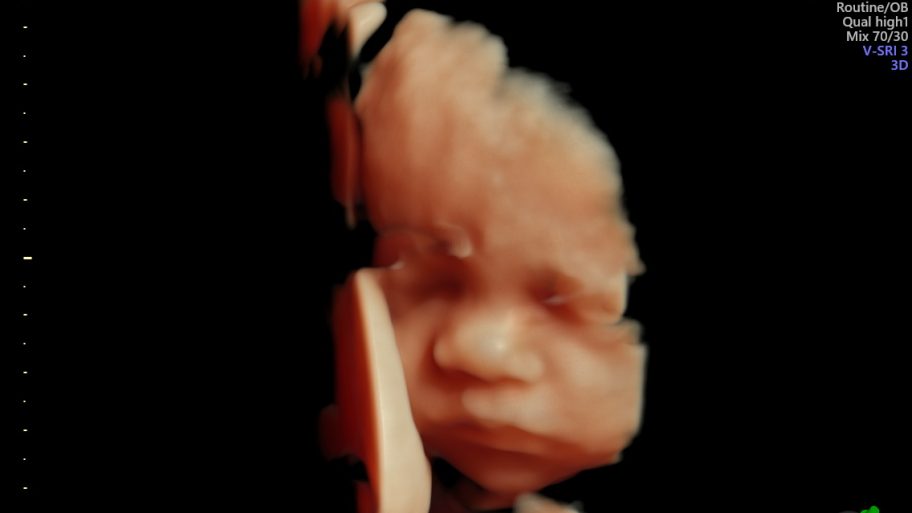

3D/4D ultrazvuk – trenutak koji ostaje zauvijek

Suvremeni 3D/4D ultrazvuk donosi novu dimenziju praćenja trudnoće. Omogućuje detaljniji prikaz razvoja djeteta prilikom svakog pregleda, a budućim roditeljima pruža priliku da na ekranu jasno vide lice svog djeteta, njegove pokrete i geste.

Iako je riječ o dijagnostičkoj metodi koja pomaže liječnicima u procjeni razvoja fetusa, taj pregled često ima i snažnu emocionalnu vrijednost, jer je to trenutak u kojem roditelji prvi put “upoznaju” svoju bebu.

U Medicu se 3D/4D ultrazvuk obavlja na najsuvremenijim uređajima visoke rezolucije koji omogućuju iznimnu jasnoću slike, a stručni tim ginekologa osigurava preciznu analizu i ugodno iskustvo pregleda.

Osim što doprinosi sigurnosti trudnoće, taj pregled mnogim roditeljima ostaje jedna od najljepših uspomena, jer je često to prvi osmijeh, zijevanje ili pokret njihove bebe koji imaju prilike vidjeti.